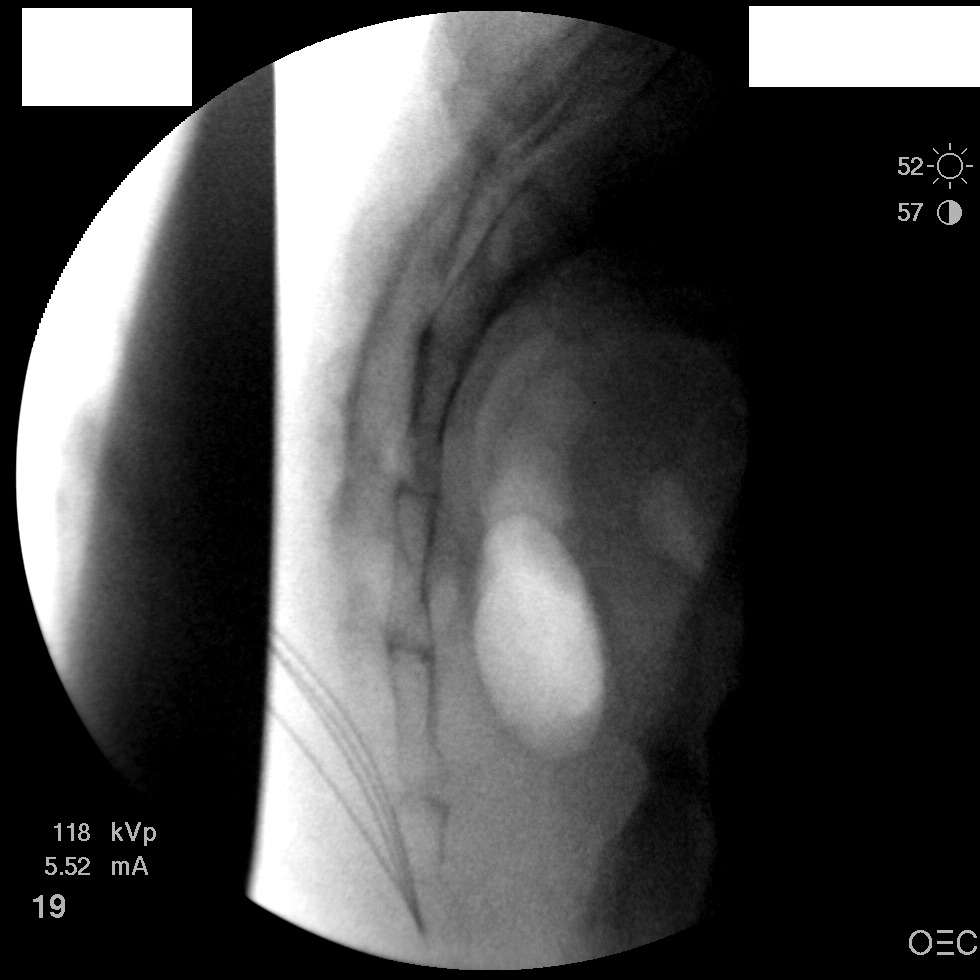

I have a patient with several months of coccyx pain. Worse with sitting, TTP over coccyx. Otherwise normal exam. No trauma, but she has an anteriorly displaced coccyx. Failed NSAIDs and no one around me does good pelvic floor PT. I scheduled her for ganglion impar injection, but her insurance won't pay for it. They wouldn't even let me to a peer-to-peer... they just straight up said they won't cover it. Any other treatment options? I don't want to send her to a surgeon. Thanks.